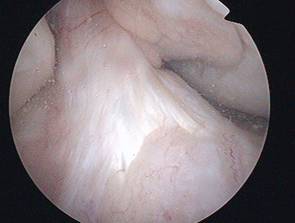

intaktes vorderes Kreuzband